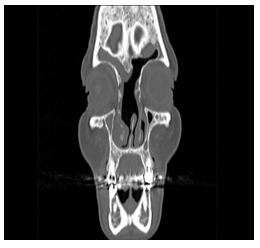

In three, the modified Lothrop technique was used to expand the margins of oncology resection due to malignant tumors that that compromised the recess and the frontal sinus. In one it was combined with an external approach. We used the optical neuronavigation system in three cases (Figure 3 & Figure 4). In 12 patients, the sinus was approached through its ostiums (inside-out), and in 4 cases the frontal sinus was drained starting from the frontal recess floor in the midline (ouside-in). One patient had a cerebrospinal fluid fistula as a complication, which was detected and repaired with free grafts with multilayer technique in the same surgical time. One patient had unilateral frontal headaches 5 years after the Lothrop modified technique surgery. A unilateral blockage of frontal drainage was identified by mucosal hyperplasia caused by its allergic fungal sinuistis (Figure 5). It was operated again by transnasal route and the sinus was permeabilized. Another patient had a complete obliteration of the frontal drainage 1 year after surgery. It was operated again with modified Lothrop technique and it was possible to wide the frontal recess drainage pathway. The other patients had a permeable frontal drainage and were asymptomatic during the average follow-up time of 3.5years. The permeability of the frontal drainage obtained with modified Lothrop technique was 87.50% (14/16), and with rescue endonasal surgery, the permeability was 100%.

Figure 5 Frontal ostium obstructions due to mucosal Hiperplasy.